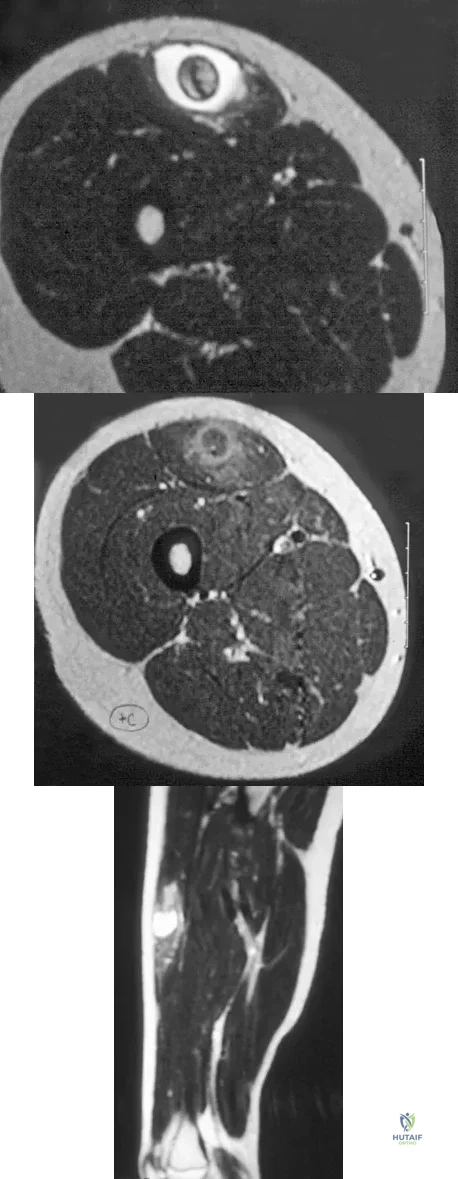

Question 50

A 12-year-old girl has had pain in her right knee for 1 month that started as activity-related and progressed to night pain. Radiographs are shown in Figures 16a and 16b, and a biopsy specimen is shown in Figure 16c. What is the recommended treatment?

Explanation